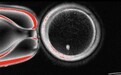

在一项实验中,研究人员在试管中用精子对82个功能性改造卵子进行受精。只有约9%的受精卵发育到了囊胚阶段。目前的所有囊胚均未进行进一步培养。